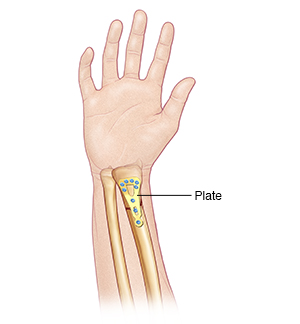

|

| A plate with tiny screws helps keep the bone stable and in place. |

Open reduction with internal fixation is a surgical procedure that may be used in cases of badly misaligned or unstable fractures, fractures involving one of the joints in the hand, or open fractures. An open fracture is one in which the skin is disrupted over a fracture, either because the bone has poked through the skin, or there is a wound over a fracture. You may be given medicine during the procedure to let you sleep and relax your muscles. Or you may have local or regional anesthesia to numb the area involved. Your healthcare provider then makes one or more cuts (incisions) to realign the bone and fix soft tissues. Pins, screws, plates, or a combination of implants may be used under the skin to hold the bone in place during healing. Another device that may be used is an external fixator. It holds the bones in the right position. It's surgically placed on the outside of the skin. It is removed or replaced with internal fixation as the injury heals.